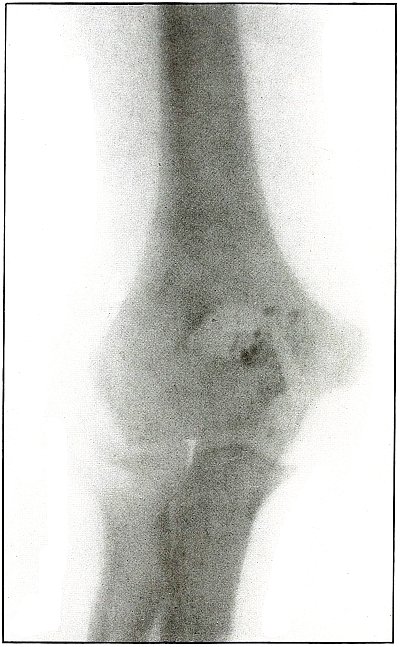

Gunshot fracture, elbow |

44 |